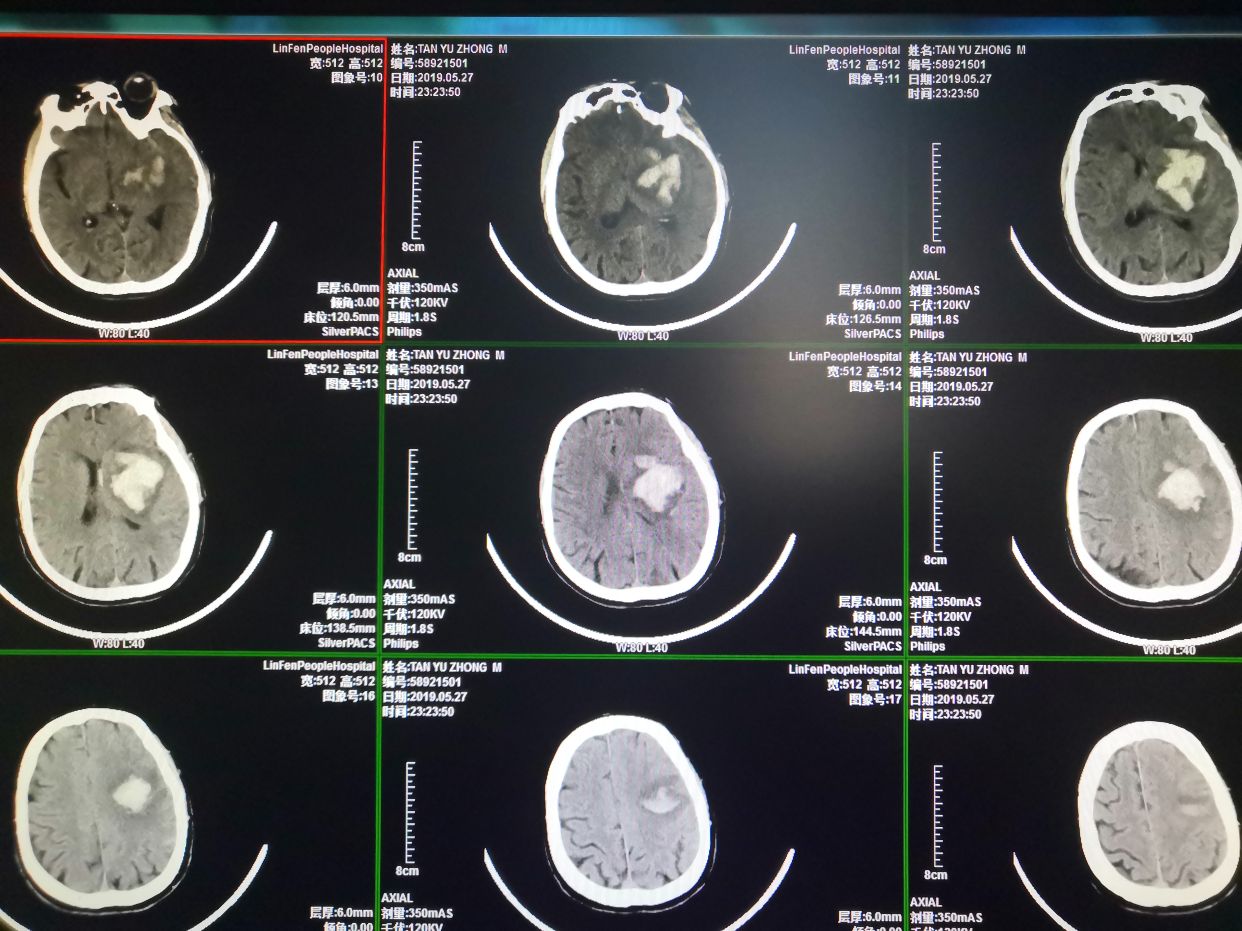

患者男性,主因:“发现意识不清伴右侧肢体无力3小时”急诊入院。患者于入院前3小时被家人发现瘫倒在发上,当时患者意识欠清,言语不能,右侧肢体无力,伴小便失禁,后被120急救后送至当地医院行颅脑CT检查,结果提示:左侧底节区脑出血,转诊至我院,复查颅脑CT后,我科急诊以:“左侧底节区脑出血高血压病3级极高危组”收治入院。查体:血压166/105mmHg,神志嗜睡,呼叫睁眼,失语,可简单遵嘱配合,双侧瞳孔等大圆,约2.5m,对光反射迟钝,口角向左侧轻度歪斜,左侧肢体肌力4级,右侧肢体肌力0级,肌张力下降,右侧肢体腱反射减弱,右侧巴氏征(+)。颅脑CT左侧底节区脑出血。诊断左侧底节区脑出血,高血压病三级极高危。

术前多田公式测量出血量约为63ml